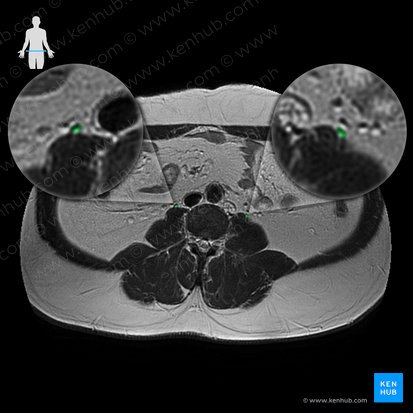

Ureter (Harnleiter)

Die paarigen Ureteren (Harnleiter) sind abgeflachte Röhren, die von den Nierenbecken zur Harnblase ziehen. Sie haben eine Länge von ca. 25-30 cm und einen Durchmesser von ca. 4-7 mm.

Im gesamten Verlauf liegt der Ureter retroperitoneal. Man unterscheidet zwischen drei Ureterabschnitten: Pars abdominalis, Pars pelvica und Pars intramuralis.